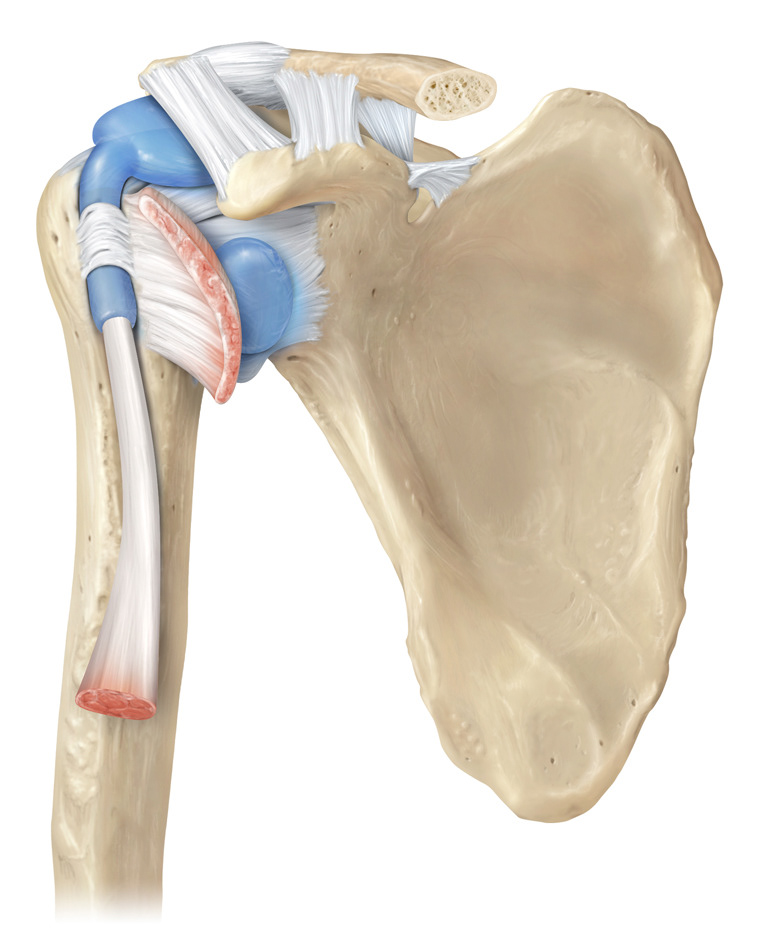

Glenohumeral ligament: анатомия и функции плечевого сустава